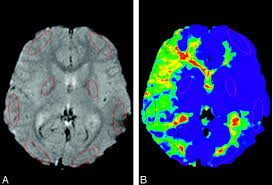

모야모야병은 뇌 기저부에 있는 주요 혈관이 점차 좁아지면서 뇌로 가는 혈류량이 줄어드는 질환입니다. 혈류가 부족해지면 뇌는 새로 가늘고 약한 혈관을 만들어 혈류를 보완하려고 하는데, 이 혈관들이 모여 있는 모습이 연기처럼 보여 ‘모야모야’라는 이름이 붙었습니다.